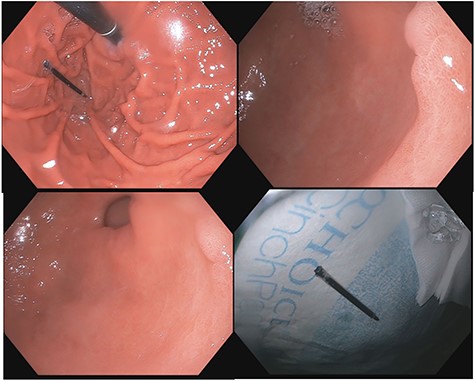

A 43-year-old incarcerated woman with borderline personality disorder and a long history of swallowing various foreign objects in periods of stress presented to the emergency department after swallowing a cup of bleach. Her surgical history was significant for multiple celiotomies for retrievals of purposefully ingested foreign bodies. During evaluation, she also admitted to swallowing an ink pen 3 weeks prior to swallowing the bleach for which she did not seek medical evaluation. She reported no food intolerance or changes in bowel function secondary to swallowing these objects. She presented with mild abdominal pain and cramping, and her vital signs and laboratory investigations were all within normal limits. Her abdominal exam was notable for mild tenderness to palpation diffusely. Computed tomography (CT) of the abdomen (Fig. 4) showed a linear foreign body in the distal gastric antrum penetrating the inferior wall and extending into the adjacent peritoneal fat. No free air or free fluid was appreciated. Initial esophagogastroduodenoscopy (EGD) was significant for mild erythema and edema to the esophageal and duodenal mucosa as a result of the caustic ingestion, and the pen was found to be deeply perforating the stomach antral wall with no associated ulcer or edema (Fig. 1). The depth at which the foreign body was lodged was uncertain, so there was concern for organ involvement outside of the gastric wall. Repeat EGD was done to assess for manifestations of esophageal, gastric or duodenal injuries from her caustic ingestion, and it revealed normal gastric mucosa (Fig. 2). A joint case was planned with the gastroenterology service for endoscopic foreign body retrieval, possible laparoscopic retrieval and gastric repair and possible open retrieval and gastric repair. The patient was taken to the operating room for the third EGD, which revealed spontaneous migration of the foreign body from the perforation site into the lumen of the gastric body (Fig. 3a). Additionally, there was spontaneous closure of the site of previous perforation (Fig. 3b and c). The ink pen was easily removed transorally using an endoscopic snare, and no further surgical intervention was required. After the procedure, the patient reported complete resolution of her abdominal pain and was able to tolerate a regular diet without problems.

Subsequent EGD 3 days later; gastric antrum with foreign body perforating through the gastric wall; normal gastric mucosa after ingestion of bleach.